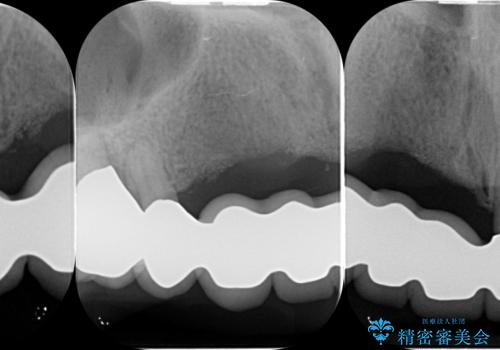

咬合性外傷による歯槽骨吸収 ブリッジ補綴

保存の難しい歯の抜歯、保存できる歯の歯周病治療、欠損部位の歯槽堤形態回復を含めブリッジによる安定した咬合機能回復を計画します。

ブリッジは欠損した部位に臨在する歯を削り、被せなければいけないというデメリットがありますが反面噛む力が強い場合連結することで強大な咬合力に対抗できるというメリットも存在します。